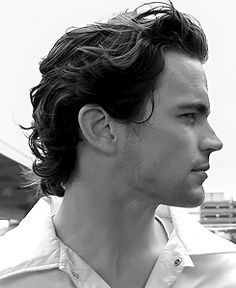

Before we jump into it I wanna show the importance of having a nice nasolabial or simply put "philtrum" curve.

It's what makes a side profile balanced - not hyper masculine but "pretty" to look at - angularity and curves in the right places make the side profile beautiful.

Before we jump into it I wanna show the importance of having a nice nasolabial or simply put "philtrum" curve.

It's what makes a side profile balanced - not hyper masculine but "pretty" to look at - angularity and curves in the right places make the side profile beautiful.